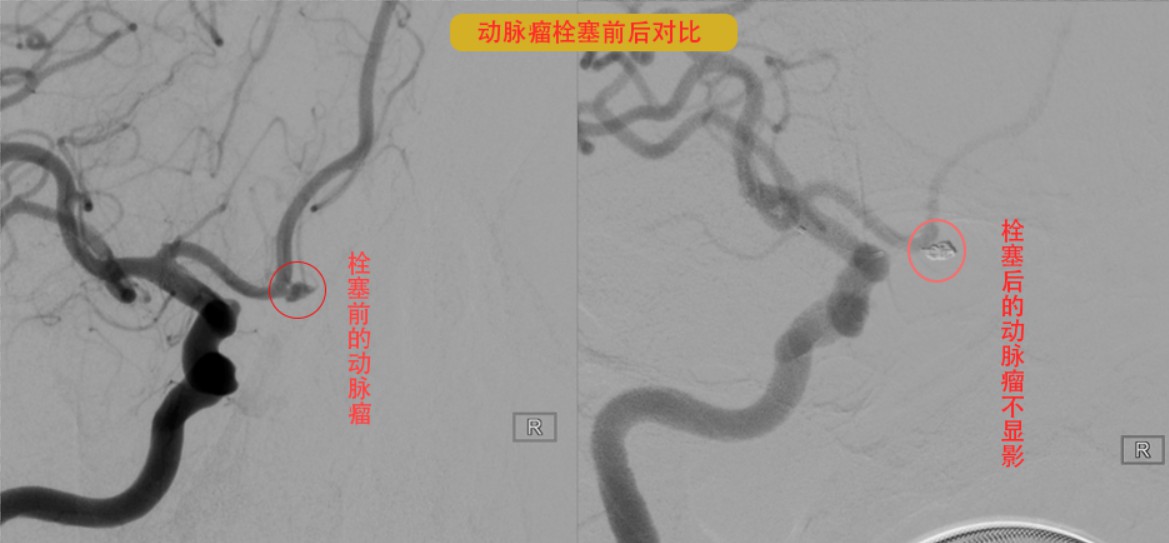

患者自发性蛛网膜下腔出血最大可能的原因就是颅内的血管病变--颅内动脉瘤破裂,须立刻完善脑血管造影检查(DSA)进一步查明出血原因,取得邹叔家属同意后,便开通绿色手术通道进行手术。